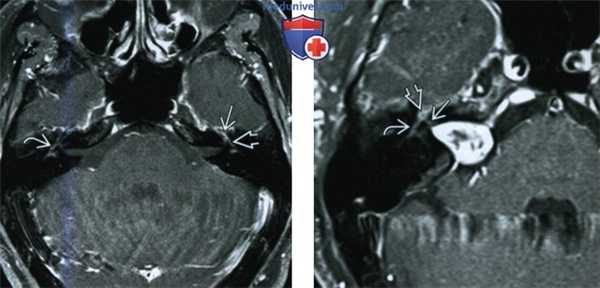

(Слева) При аксиальной МРТ Т1 ВИ С+ FS на уровне внутренних слуховых каналов определяется нормальное контрастное усиление коленчатого ганглия и переднего барабанного сегмента ЧН VII слева. Справа определяется нормальное контрастное усиление переднего барабанного сегмента.

(Справа) При аксиальной MPT Т1 ВИ С+ FS у пациента с правосторонней вестибулярной шванномой определяется повышенное контрастирование лабиринтного, переднего тимпанического сегмента ЧН VII, и коленчатого ганглия.

(Слева) При корональной МРТ Т1 ВИ С+ FS на уровне преддверий определяется нормальное контрастирование среднего барабанного сегмента лицевых нервов.

(Справа) При корональной МРТ Т1ВИ С+ FS у этого же пациента определяется нормальное контрастирование коленчатого ганглия сразу же над улиткой. Обратите внимание на мышцы, напрягающие барабанную перепонку, накапливающие контраст с обеих сторон. При ЗТ нормальное контрастное усиление структур височной кости более выражено.